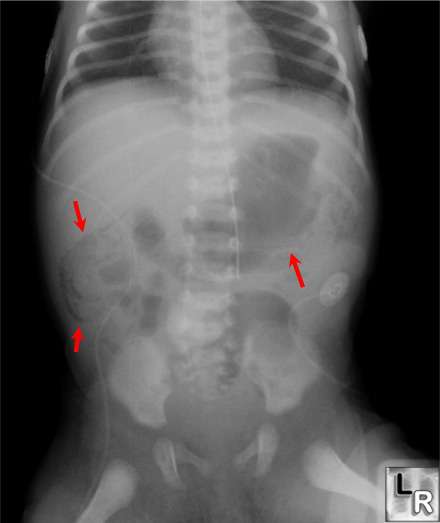

ينجم تهوي الأمعاء pneumatosis intestinalis (استرواح الأمعاء) عن إنتاج الغاز في جدار الأمعاء . و يمكن التحري عنه بصورة البطن الشعاعية و يعتبر تهوي الأمعاء علامة واسمة لالتهاب الكولون و الأمعاء النخري عند الخدج.

و يعتبر تهوي الأمعاء علامة واسمة و مشخصة لالتهاب الكولون و الأمعاء النخري على الصورة الشعاعية عند الخدج.

و تجرى الصور الشعاعية للبطن كل 6 ساعات على الأقل لمراقبة تهوي الأمعاء و وجود الهواء في وريد الباب و الهواء الحر في جوف الصفاق .